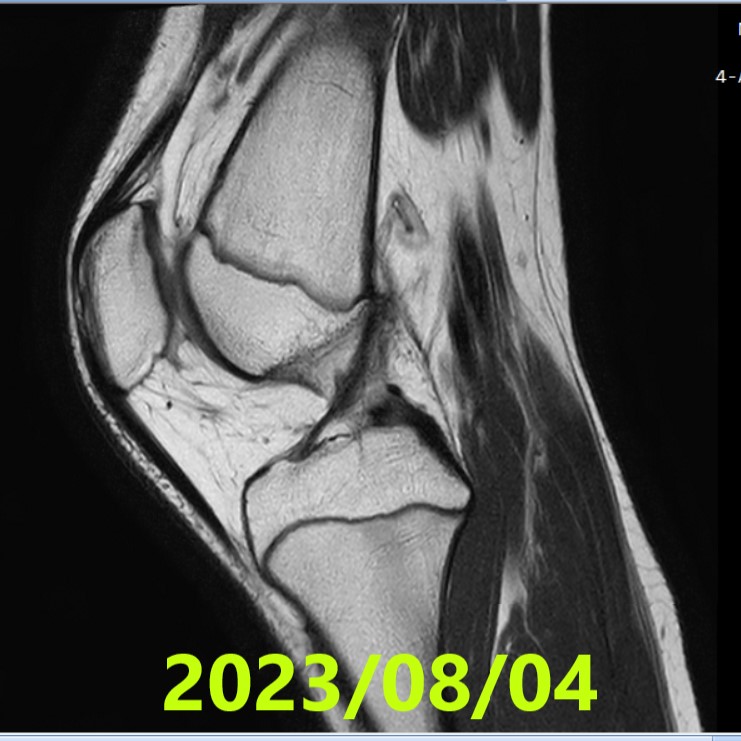

- Data: 2 agosto 2023 (RM n.2)

- Letture indipendenti (3 radiologi): concordi, ACLOAS grado 2.

- Reperti: continuità ripristinata; non spessore pieno, ma spessore e tensione legamentosa definiti.

- RM n.2 (2023/08/02): ACLOAS grado 2 (concorde, 3/3 lettori).